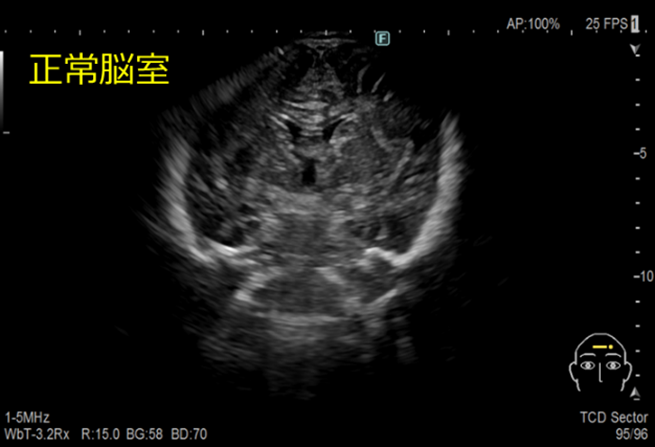

経頭蓋超音波検査

頭蓋骨早期癒合症の有無、頭蓋内の病変の有無や性状などについて観察しています。

- 大泉門が開大している乳児に対して行います。大泉門が閉鎖する乳児以降では観察が困難となります。

- 検査時は、頭が動いてしまうと検査ができないため、保護者の方に頭部の保持をお願いしています。

水頭症とは

髄液が頭蓋内腔に過剰に貯留した状態のことです。

脳室拡大、頭蓋内圧亢進、脳実質の圧迫などが見られます。